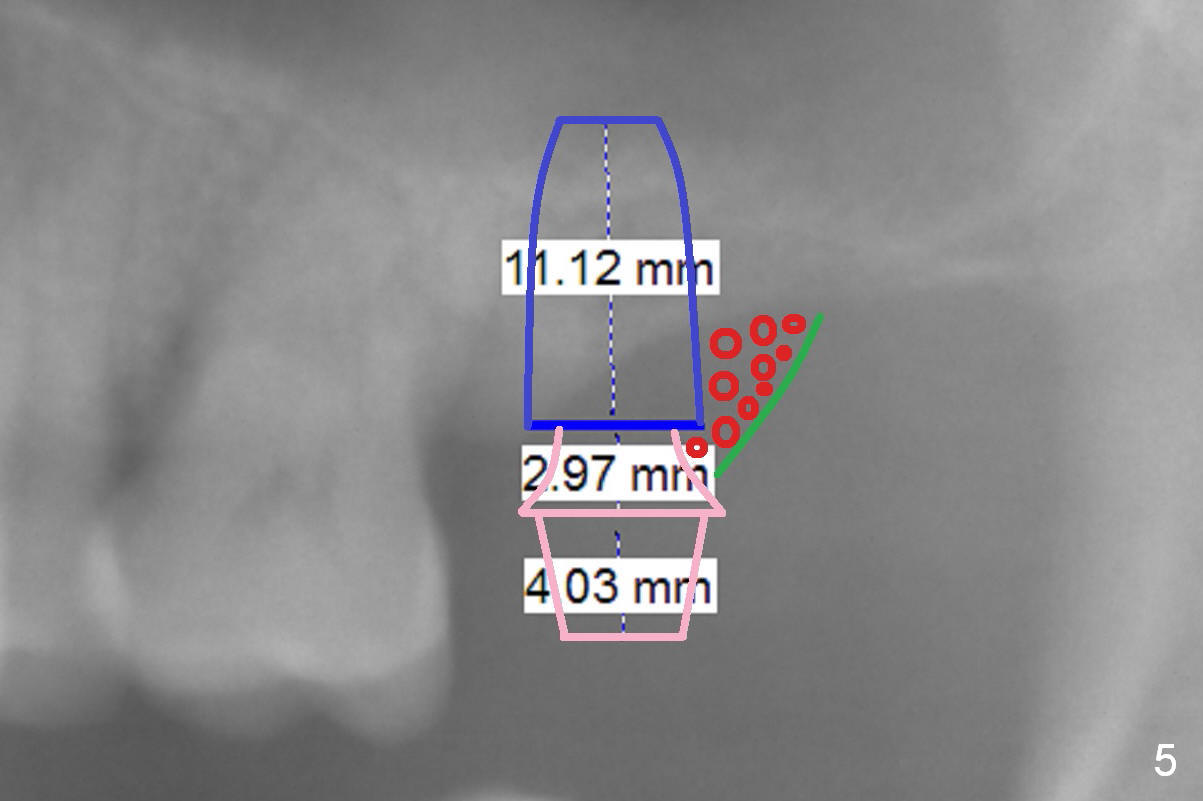

A 54-year-old man has crowded dentition with moderate to advanced periodontitis (Fig.1) and bruxism (exostosis (Fig.6 *)). It is essential to re-establish complete dentition by placing implants at #6, 7 and 15 initially and more when other teeth are lost. The ridge at #6 and 7 is moderately atrophic (Fig.7), while that at #15 severely atrophic (Fig.8). Due to narrow mesiodistal space at #6 and 7 (Fig.2), narrow and 1-piece implants may have to be placed (Fig.3).

The bone height at #15 is unfavorable (Fig.4). Use 1.6 mm drill for 6 mm to start osteotomy, followed by Magic Expanders (BEB). Since the restorative height is limited due to long-standing edentulism with the supraerupted opposing tooth (Fig.5), consider using Magicore (blue). Use the bone condenser with stopper from Sinus Master kit for sinus lift. Place bone graft distally (red circles), followed by resorbable and nonresorbable collagen membranes (green curved line).